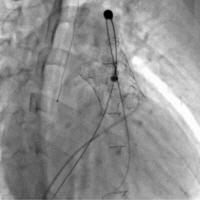

[사진2] 경피적 폐동맥판막 치환술(PPVI) 시술 장면. 카테터를 통해 폐동맥판막 위치에 인공 판막을 삽입하는 모습

경피적 폐동맥판막 치환술은 가슴을 열지 않고 허벅지 정맥을 통해 카테터로 인공 판막을 삽입하는 최소 침습 치료다. 선천성 심장병 환자 가운데 폐동맥판막 기능이 저하된 경우 시행되며, 반복적인 개흉·개심수술을 대신하거나 시점을 늦출 수 있는 치료 방법으로 활용되고 있다.